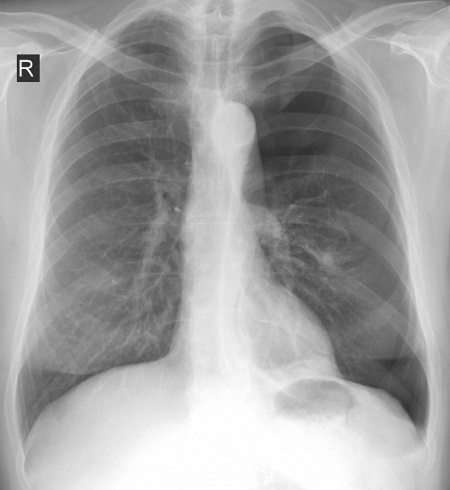

В рентгенологический кабинет клиники №1 Витерра Беляево к врачу - рентгенологу обратился мужчина К. 59 лет, с жалобами на дискомфорт и болевые ощущения в грудной клетке, а также невозможность произвести глубокий вдох. Данные симптомы беспокоят его на протяжении 2-х недель (!!!). Хронические заболевания органов грудной клетки отрицает.

При выполнении рентгенографии органов грудной клетки в 2-х проекциях определяется классическая картина левостороннего среднего пневмоторакса.

Пациент госпитализирован в стационар для проведения хирургического лечения и дальнейшего дообследования с целью выяснения причин возникновения спонтанного пневмоторакса.